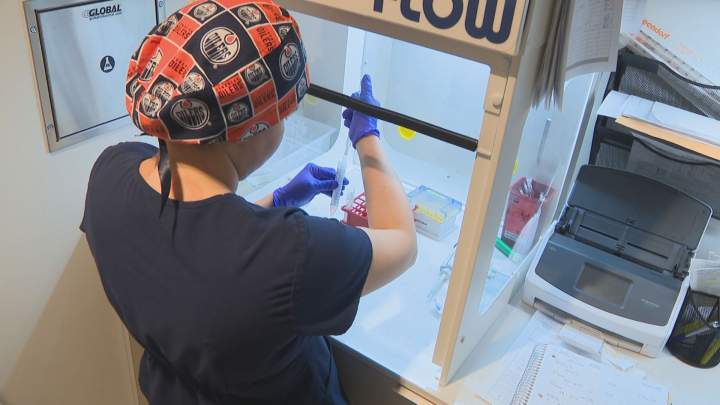

Alberta woman shares expensive, ‘devastating’ fertility journey in hopes of helping othersBreanne Irving, 36, has always wanted to be a mom and has spent over $50,000 on fertility treatments — a process she wishes she'd started sooner and wants others to be aware of.HealthApr 23, 2025